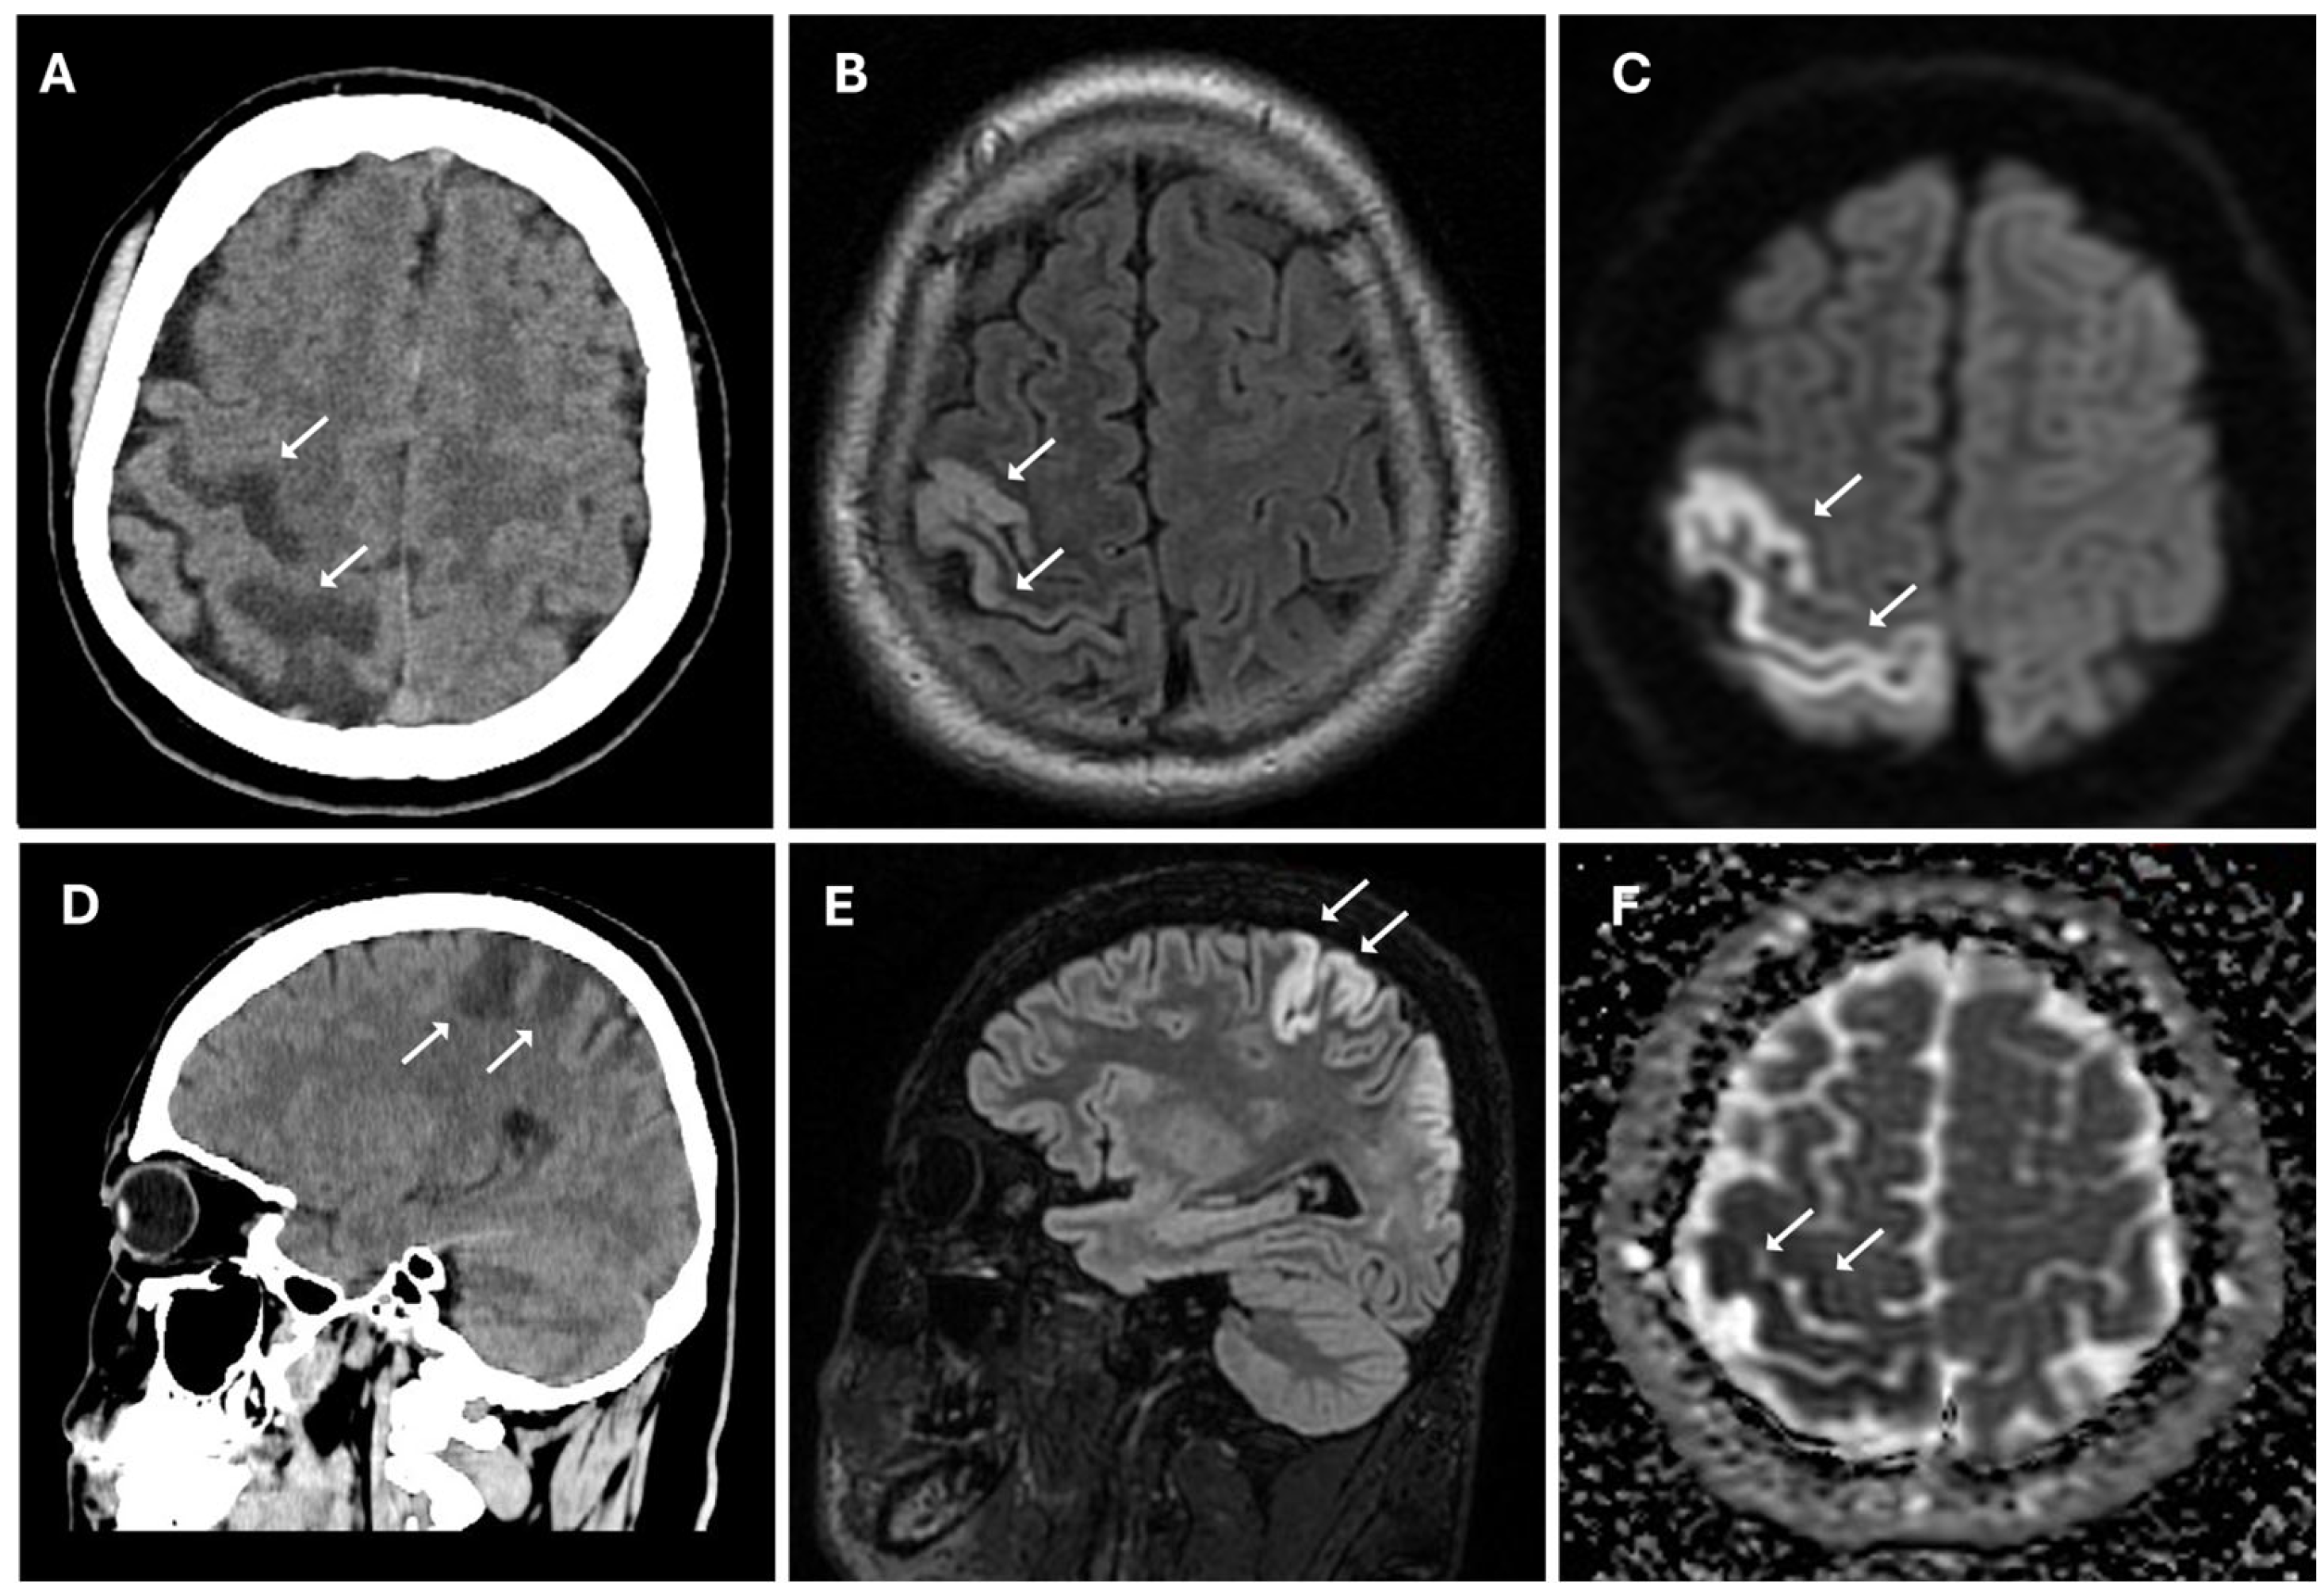

The patient underwent multi-detector computed tomography (MDCT, Optima 64 slice, GE Healthcare, Milwaukee, WI, USA) (Table S1) of the brain for suspected stroke. A CT scan revealed the presence of cortico-subcortical hypodensities in the right frontal and parietal regions, in the deep white matter of the right periventricular area, associated with swelling of the cerebral cortex and obliteration of subarachnoid spaces (Figure 1).

Figure 1. Acute ischemic lesion in the right frontoparietal region involving both the precentral and postcentral gyri. (A,D) Non-enhanced CT scan in axial (A) and sagittal (D) plans show hypodensity area (white arrows) in the right frontoparietal cortex and subcortical white matter, consistent with early ischemic changes. (B,E) Axial (B) and sagittal (E) 3D FLAIR sequences show hyperintense signal (white arrows) in cortical and subcortical areas, indicative of edema in the context of an evolving infarct. (C,F) Diffusion-weighted imaging (C) reveals marked hyperintensity (white arrows), while the corresponding apparent diffusion coefficient map (F) shows hypointensity (white arrows), confirming true restricted diffusion compatible with acute ischemia (cytotoxic edema).

CT findings raised the suspicion of vaso-occlusive disease, and, in particular, moyamoya disease; to exclude secondary causes of moyamoya disease, the following parameters were also evaluated: autoimmune panel (ANA, ENA, anti-dsDNA, and ANCA), thyroid function and antibodies (TSH, FT3, FT4, and anti-TPO), infectious screening (HBV, HCV, HIV, and syphilis), and thrombophilia panel; all of these parameters showed normal values. Subsequently, the patient underwent MRI, MRA, and DSA examinations. MR examination (performed with a Signa HDxT MR scanner, GE Healthcare, Milwaukee, WI, USA) showed the presence of hyperintense areas on T2-weighted and FLAIR sequences, with true restricted diffusion (increased signal on DWI sequences and reduced ADC values), located in right prefrontal, superior frontal, and postcentral gyrus; in the right periventricular and supraventricular white matter; and at the level of the splenium of the corpus callosum (Figure 1); the cerebral cortex also showed a swollen appearance in these regions, confirming recent ischemic lesions. A small hypointense area on T2*-weighted sequences was also identified at the level of the aforementioned altered signal area of the right supraventricular white matter. This area was also hyperintense on T1-weighted sequences, indicating a subacute hemorrhagic lesion. Moreover, chronic ischemic lesions, characterized by hyperintensity on T2-weighted and FLAIR sequences, with no diffusion restriction, were detected in the right parietal, occipital, and temporal cortico-subcortical regions (Figure 3).